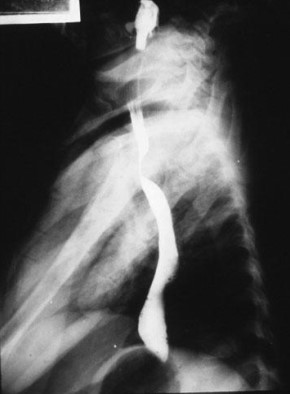

Common abdominal X-ray findings: